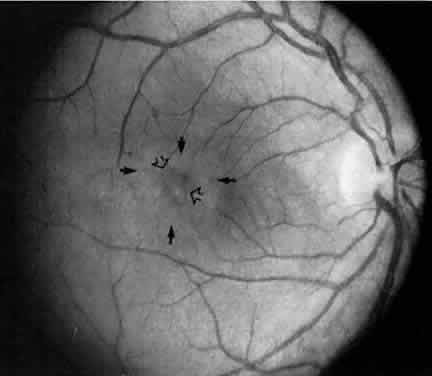

Retinal changes that can occur in pars planitis include perivascular sheathing of the retinal venules (periphlebitis), cystoid macular edema, and optic disc edema (Figs. 3 and 4). In cases of chronic cystoid macular edema, epiretinal membrane formation often occurs.4,13,27

Fig. 3. Pars planitis. Cystoid macular edema. Black arrows point to a halo of edema surrounding the macula. Open arrows point to cysts in the macula.

Fig. 4. Pars planitis. Fluorescein angiogram showing a petaloid staining pattern in the macula.